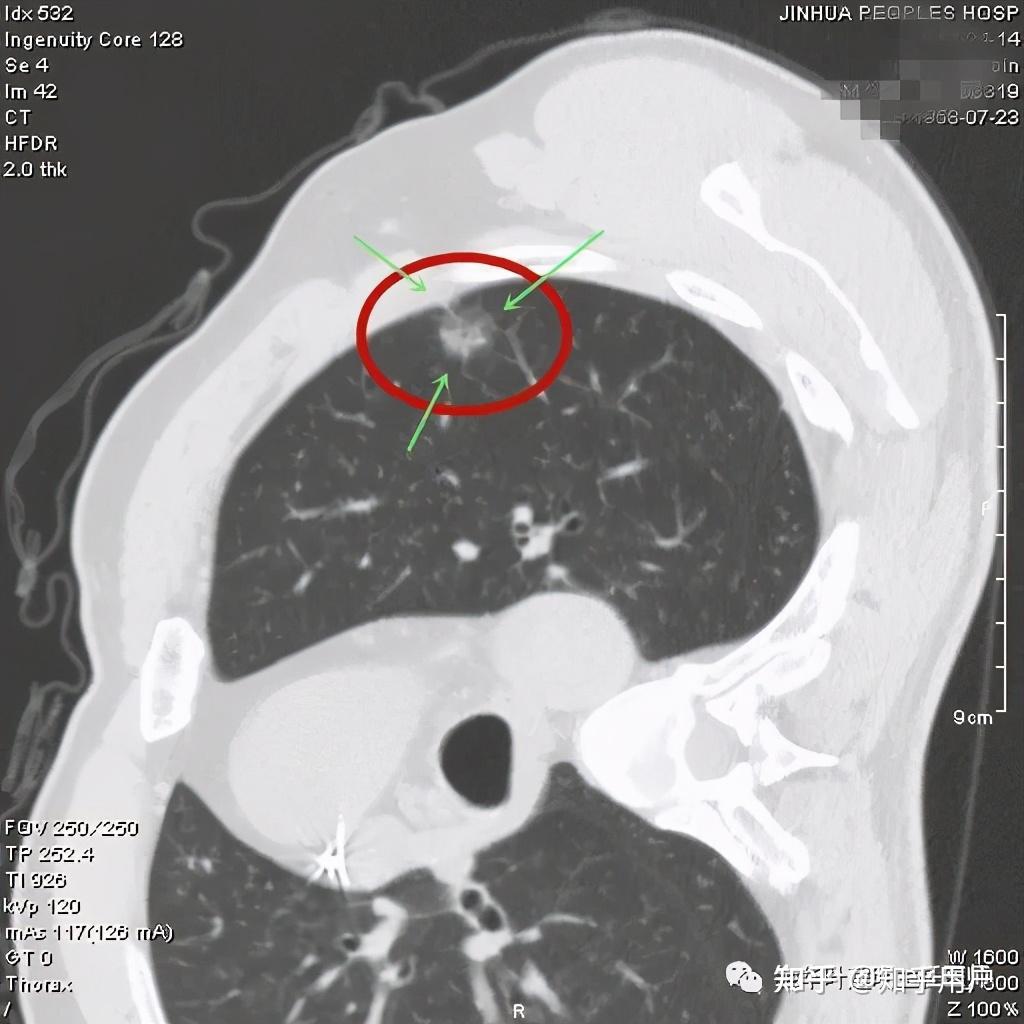

看着,非常不错,以后原位腺癌与非典型增生不是癌了,不需要手术了,至少不能按恶性肿瘤的方式进行手术了。这是好事!但真的到了临床上,如何把握,我看仍是前路漫漫,迷雾重重!我们先举几个例子,来看看影像上如何来区分AAH、AIS、MIA以及浸润性腺癌。下面的四幅CT图分别各是其中的一种,是我们术后有病理依据确诊的病例,你能分出哪张是哪种吗?

有没有高手能分辨出来?我是一头雾水,根本分不清到底哪个是哪种。都是纯磨玻璃结节,都是瘤肺边界清楚,大小都在1厘米左右或以下。现比如下面这四幅CT图也是分别为AAH、AIS、MIA以及浸润性腺癌(贴壁型),你能分得清楚哪幅图是哪种吗?

这几乎就是四胞胎,长的没什么区别,但病理类型天差地别。现在把AAH与AIS剔除出恶性肿瘤后,更是差别巨大了,是癌与非癌的区别了,但没有手术切除病检的情况下,你如何来区分?